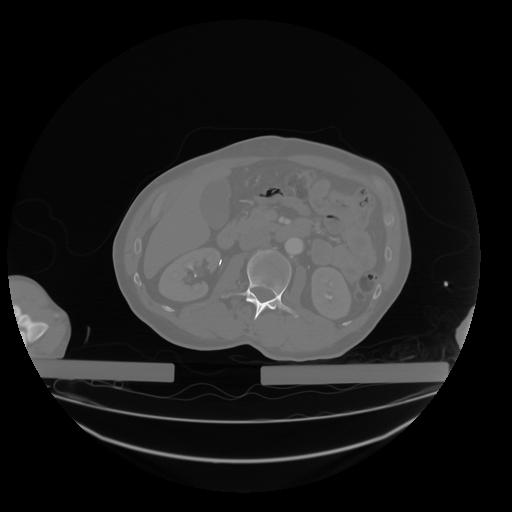

28 CUERPO,CE,Vol,2.0,CUERPO,,